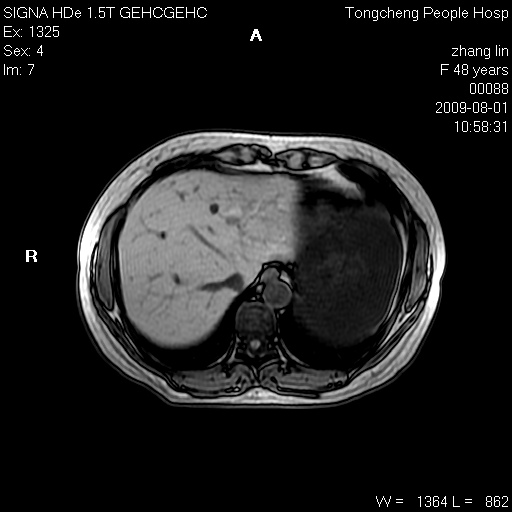

女,48岁。健康体检,彩超发现右肾占位性病变。平素健康。

临床诊断:右肾占位性病变,性质待定(囊肿?肿瘤?)。

上中腹部mr平扫+增强扫描,图像如下:

右肾上极见一类圆形病灶,t1wi呈等信号t2wi呈等高混杂信号,三期增强无强化,边界清---考虑囊肿出血。

同反相位均表现为等信号,病变无强化,考虑含蛋白的囊肿可能,弥散加权相或许有些帮助,